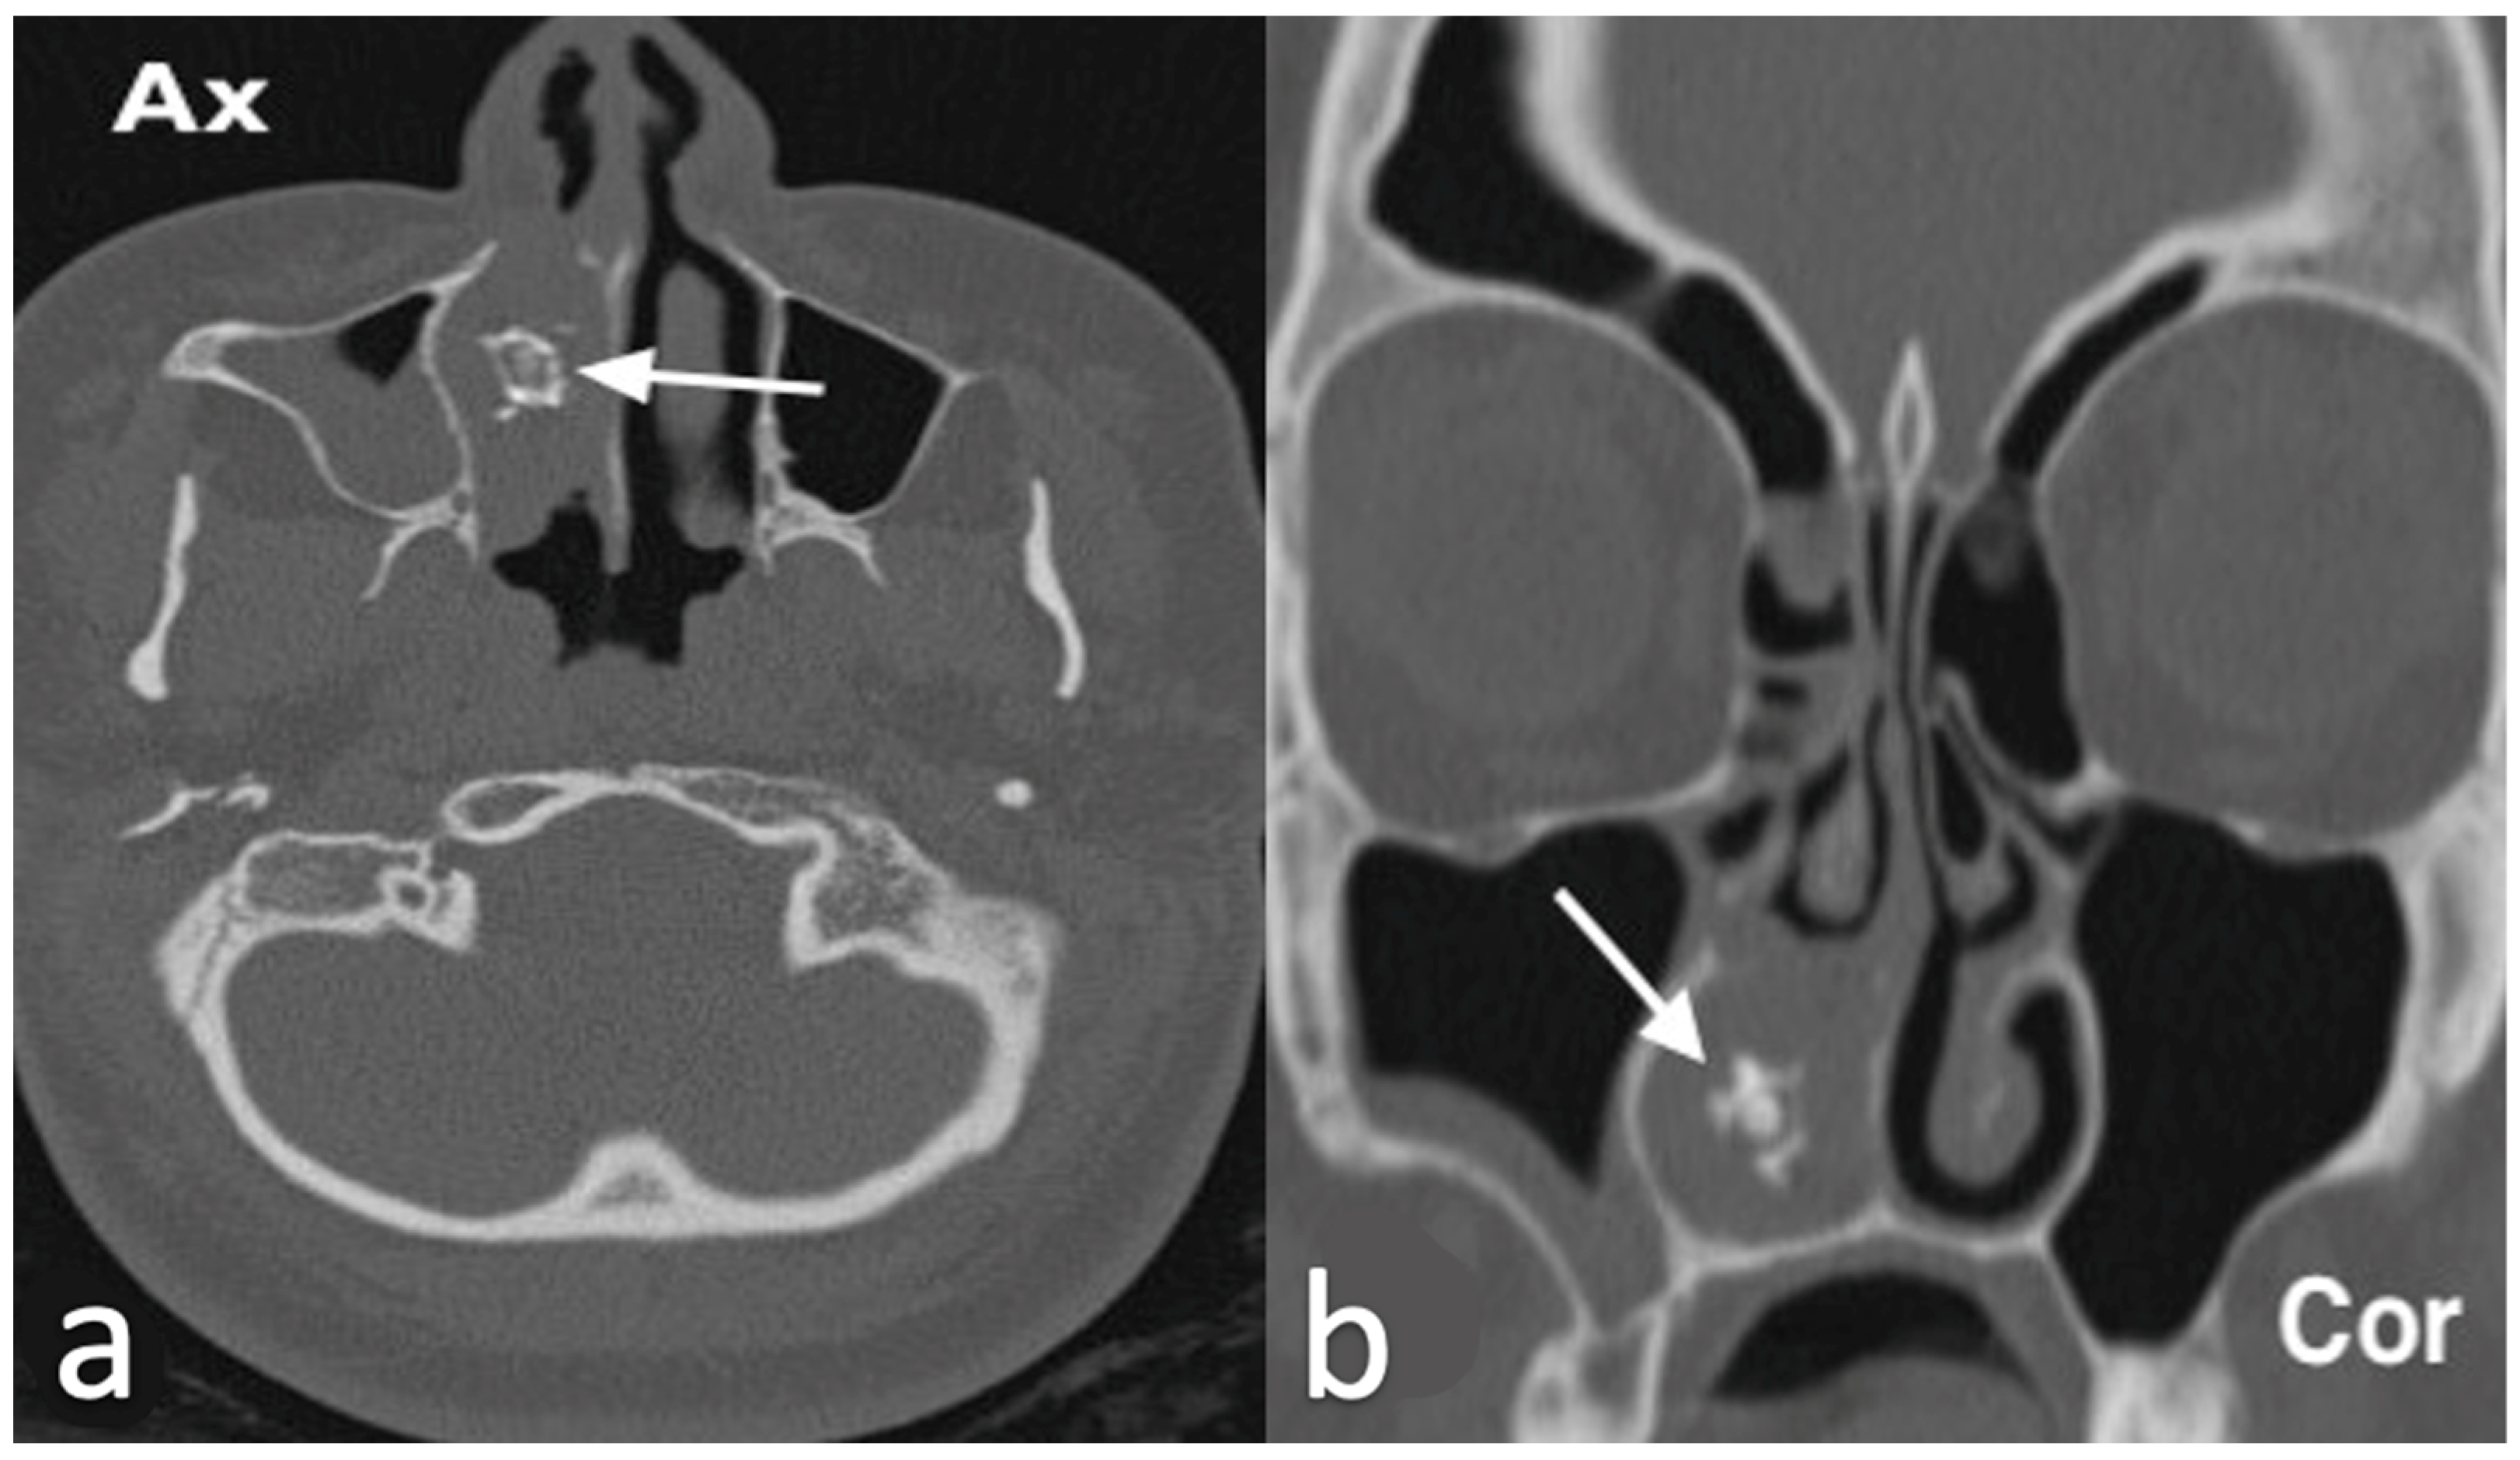

3.1.2. Rinolith

3.1.3. Inverted Mesiodens